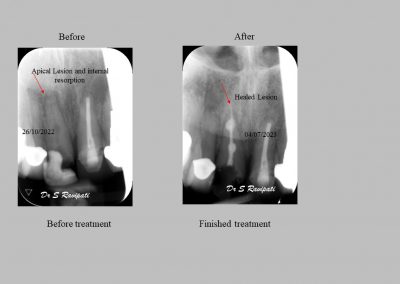

The main goal of endodontic therapy is to remove necrotic pulp tissues, to eliminate or significantly reduce microorganisms and their toxic products from the canals and also to prevent inflammatory lesion in the periapical area. Endodontic therapy protects the tooth from further invasion from microorganisms. If the tooth is left without treating, the infection may spread and cause pain and swelling.

During the consultation, the dentist will first listen to your concerns and carry out appropriate tests to identify the right tooth that is causing pain. As a part of the diagnosis, your dentist will carry out various clinical tests to identify the right tooth and will take some radiographs which can aid in the diagnosis.

Studies have shown thorough cleaning with instruments, disinfection and sealing the canals contribute to the successful healing of the infection and this success is reported as 95%.